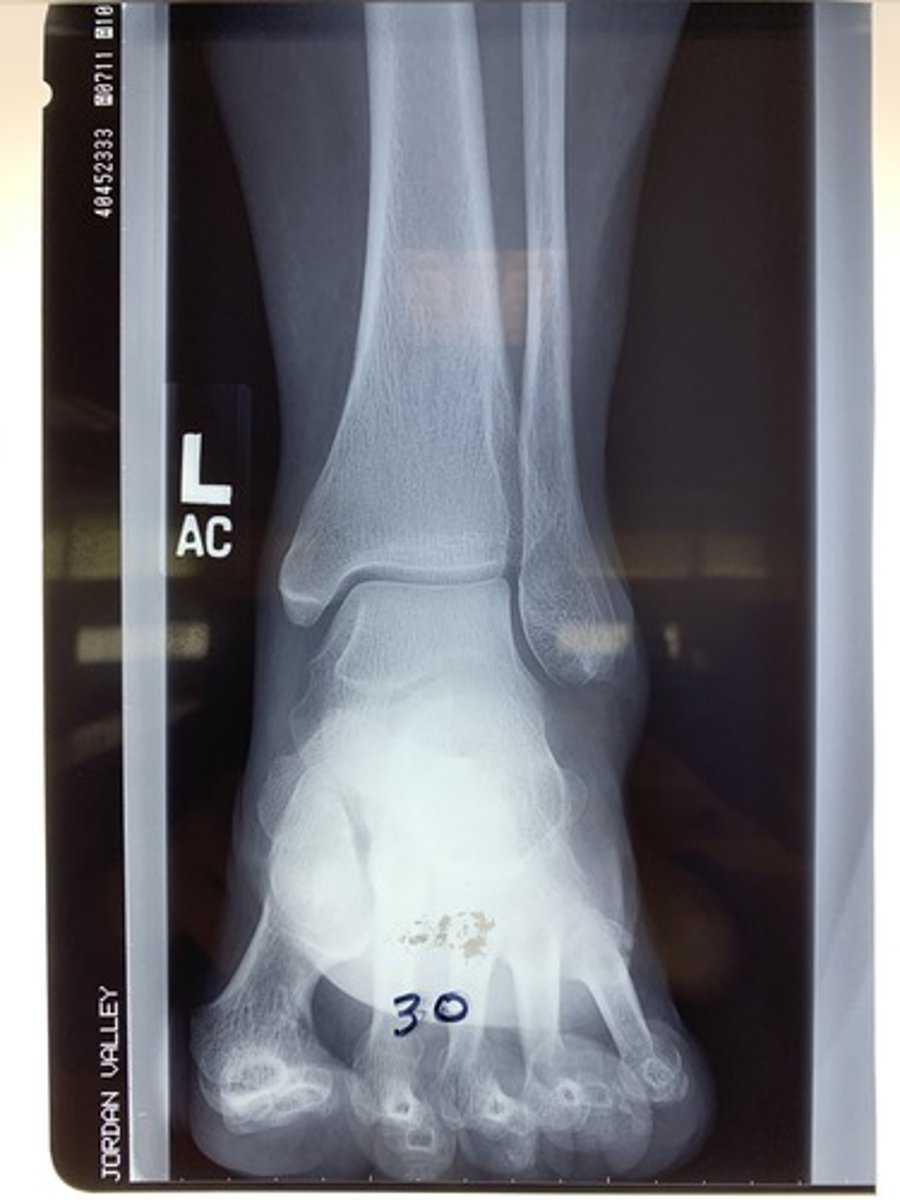

Is radiograph 30 acceptable, underexposed (inadequate mAs), or under-penetrated (inadequate kVp)?

acceptable